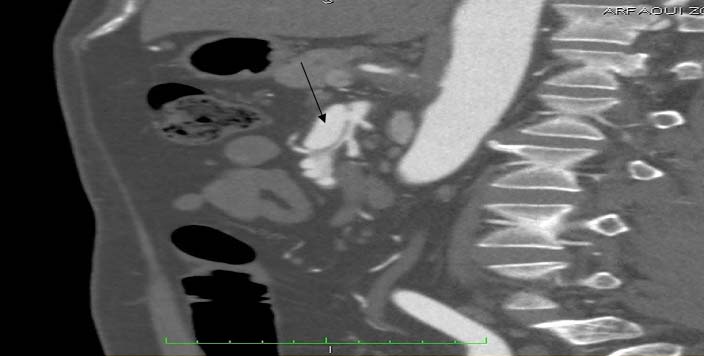

Dissection of SMA was extending for approximately 1.8cm, accompanied by contrast accumulation in the wall due to ulceration in the proximal part of the artery. SMA was visualized as 60% narrowed because of the dissection [Table/Fig-4,5 and 6]. Inferior Mesenteric Artery (IMA) and renal arteries were normal. Conservative treatment was the method of choice. It was based on anticoagulation, pain and hypertension control. His abdominal pain resolved in 2 days. The patient was discharged home with warfarin and aspirin. Follow-up CT scan at 3 and 6 months demonstrated that the dissections and aneurysmal dilatation were both stable. The patient was continuing to do well on his 15 month clinical follow-up. Further follow-up CT examinations were planned.

Abdominal 4 CT scan with IV contrast (Longitudinal view) demonstrates a dissection of SMA with Partial thrombosis causing 60% stenosis.